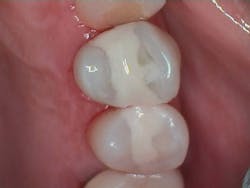

Figure 3 shows the final restoration immediately after placement. Figure 4 shows the final restoration of an initial caries lesion on the buccal. The clinician anticipated maturation of the glass-hybrid in choosing a lighter shade of A2, which initially appeared much too light. A slightly darker shade may have been more appropriate.

Figure 5 is a 36-month follow-up bitewing radiograph demonstrating excellent support of the significantly undermined enamel and deposition of secondary dentin in the mesial pulp horns. Figures 6 and 7 show the occlusal and facial restorations respectively after 18 months. Notice the improvement in shade.